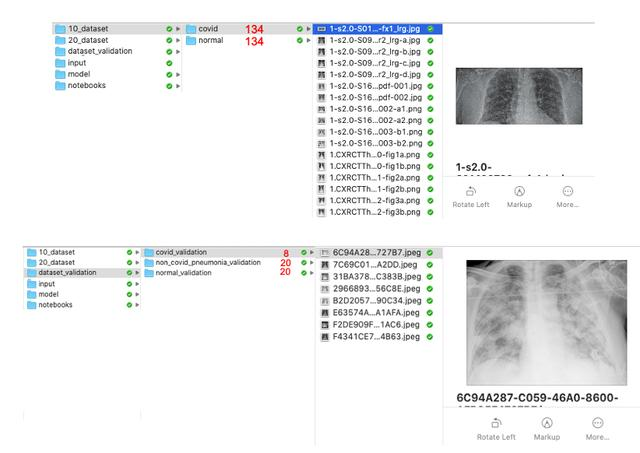

按照以下说明,134个选定图像将被复制到文件夹../10_dataset/covid/。

input_dataset_path = '../input/10_Covid_images/images'output_dataset_path = '../dataset/covid'dataset = xray_cv_traincol_img_name = 'filename'load_image_folder(dataset, col_img_name, input_dataset_path, output_dataset_path)

在../input/20_Chest_Xray/train/NORMAL文件夹重复同样的过程,我们将随机复制用于训练的相同数量图像 (len (xray_cv_train)),134个图像,这样用于训练模型的数据集是平衡的。

input_dataset_path = '../input/20_Chest_Xray/train/NORMAL'output_dataset_path = '../dataset/normal'img_num_select = len(xray_cv_train)load_image_folder_direct(input_dataset_path, output_dataset_path, img_num_select)

以同样的方式,我们分离出20个随机图像,以供以后在模型验证中使用。

input_dataset_path = '../input/20_Chest_Xray/train/NORMAL'output_dataset_path = '../dataset_validation/normal_validation'img_num_select = 20load_image_folder_direct(input_dataset_path, output_dataset_path, img_num_select)

尽管我们没有用显示肺炎症状的图像(Covid-19)来训练模型,但是观察最终模型如何与肺炎症状一起工作是很有趣的,因此我们还分离了其中的20幅图像,以供验证。

input_dataset_path = '../input/20_Chest_Xray/train/PNEUMONIA'output_dataset_path = '../dataset_validation/non_covid_pneumonia_validation'img_num_select = 20load_image_folder_direct(input_dataset_path, output_dataset_path, img_num_select)

下面的图片显示了在这个步骤结束时应该如何配置文件夹(无论如何在我的Mac上),此外红色标记的数字显示文件夹中包含的x光图像的相应数量。